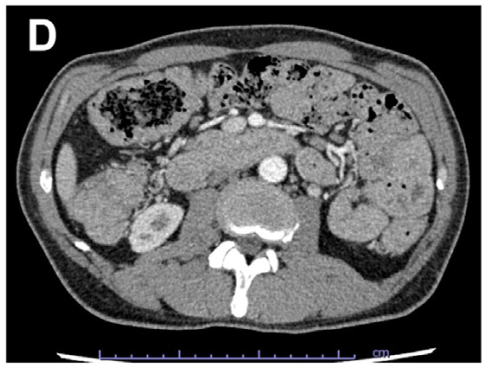

病史摘要:30岁男性,因“上腹不适6月,腹胀20天”入院。6月前无诱因出现上腹部不适、进食后腹胀,外院胃镜示反流性食管炎,肝功异常,对症治疗缓解。20天前出现全腹胀、黄疸、食欲降低、双下肢水肿。既往青霉素过敏,有吸烟、饮酒史,曾长期在高原工作。 诊疗过程:入院查体生命体征平稳,全身皮肤巩膜黄染,腹部膨隆,移动性浊音阳性。辅助检查提示布加综合征、肝硬化等。诊断为慢加急性